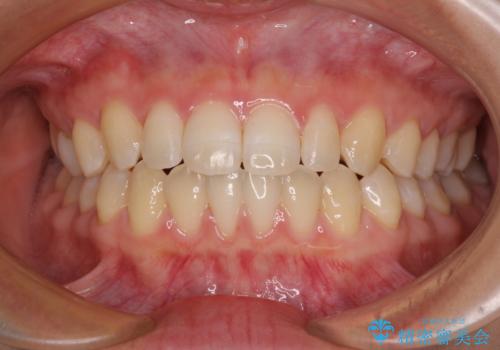

隙間だらけの歯列 インビザラインで改善

空隙歯列(すきっ歯)は、舌の突出癖をある程度改善できたとしても、後戻りにより隙間が開きやすいと言われています。

裏側から細いワイヤーで保定するとともに、睡眠時のマウスピース装着を徹底していただくことで、後戻りを最小限にとどめます。